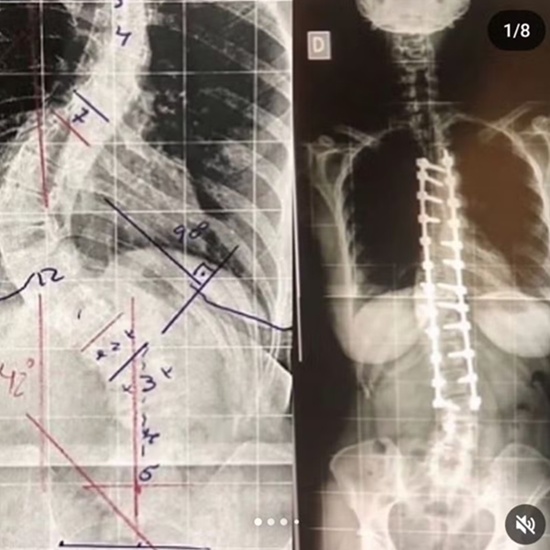

Dani Guedes, 44 anos, entrou em detalhes sobre a cirurgia que realizou para reparar uma escoliose de quase 90 graus. A atriz saiu da operação com 24 pinos e duas hastes.

A cirurgia da atriz foi feita em 2018. Dani recomenda o procedimento a quem enfrenta os mesmos desafios que ela.

“A cirurgia levou 10 horas, minha escoliose estava com 90 graus. O resultado do que era a curvatura para o que ficou foi excelente. Mas meu cérebro não entende até hoje que estou reta. Então, agora, me sinto torta. Fiquei com diferença na perna e manco um pouco quando cansada”, destacou.